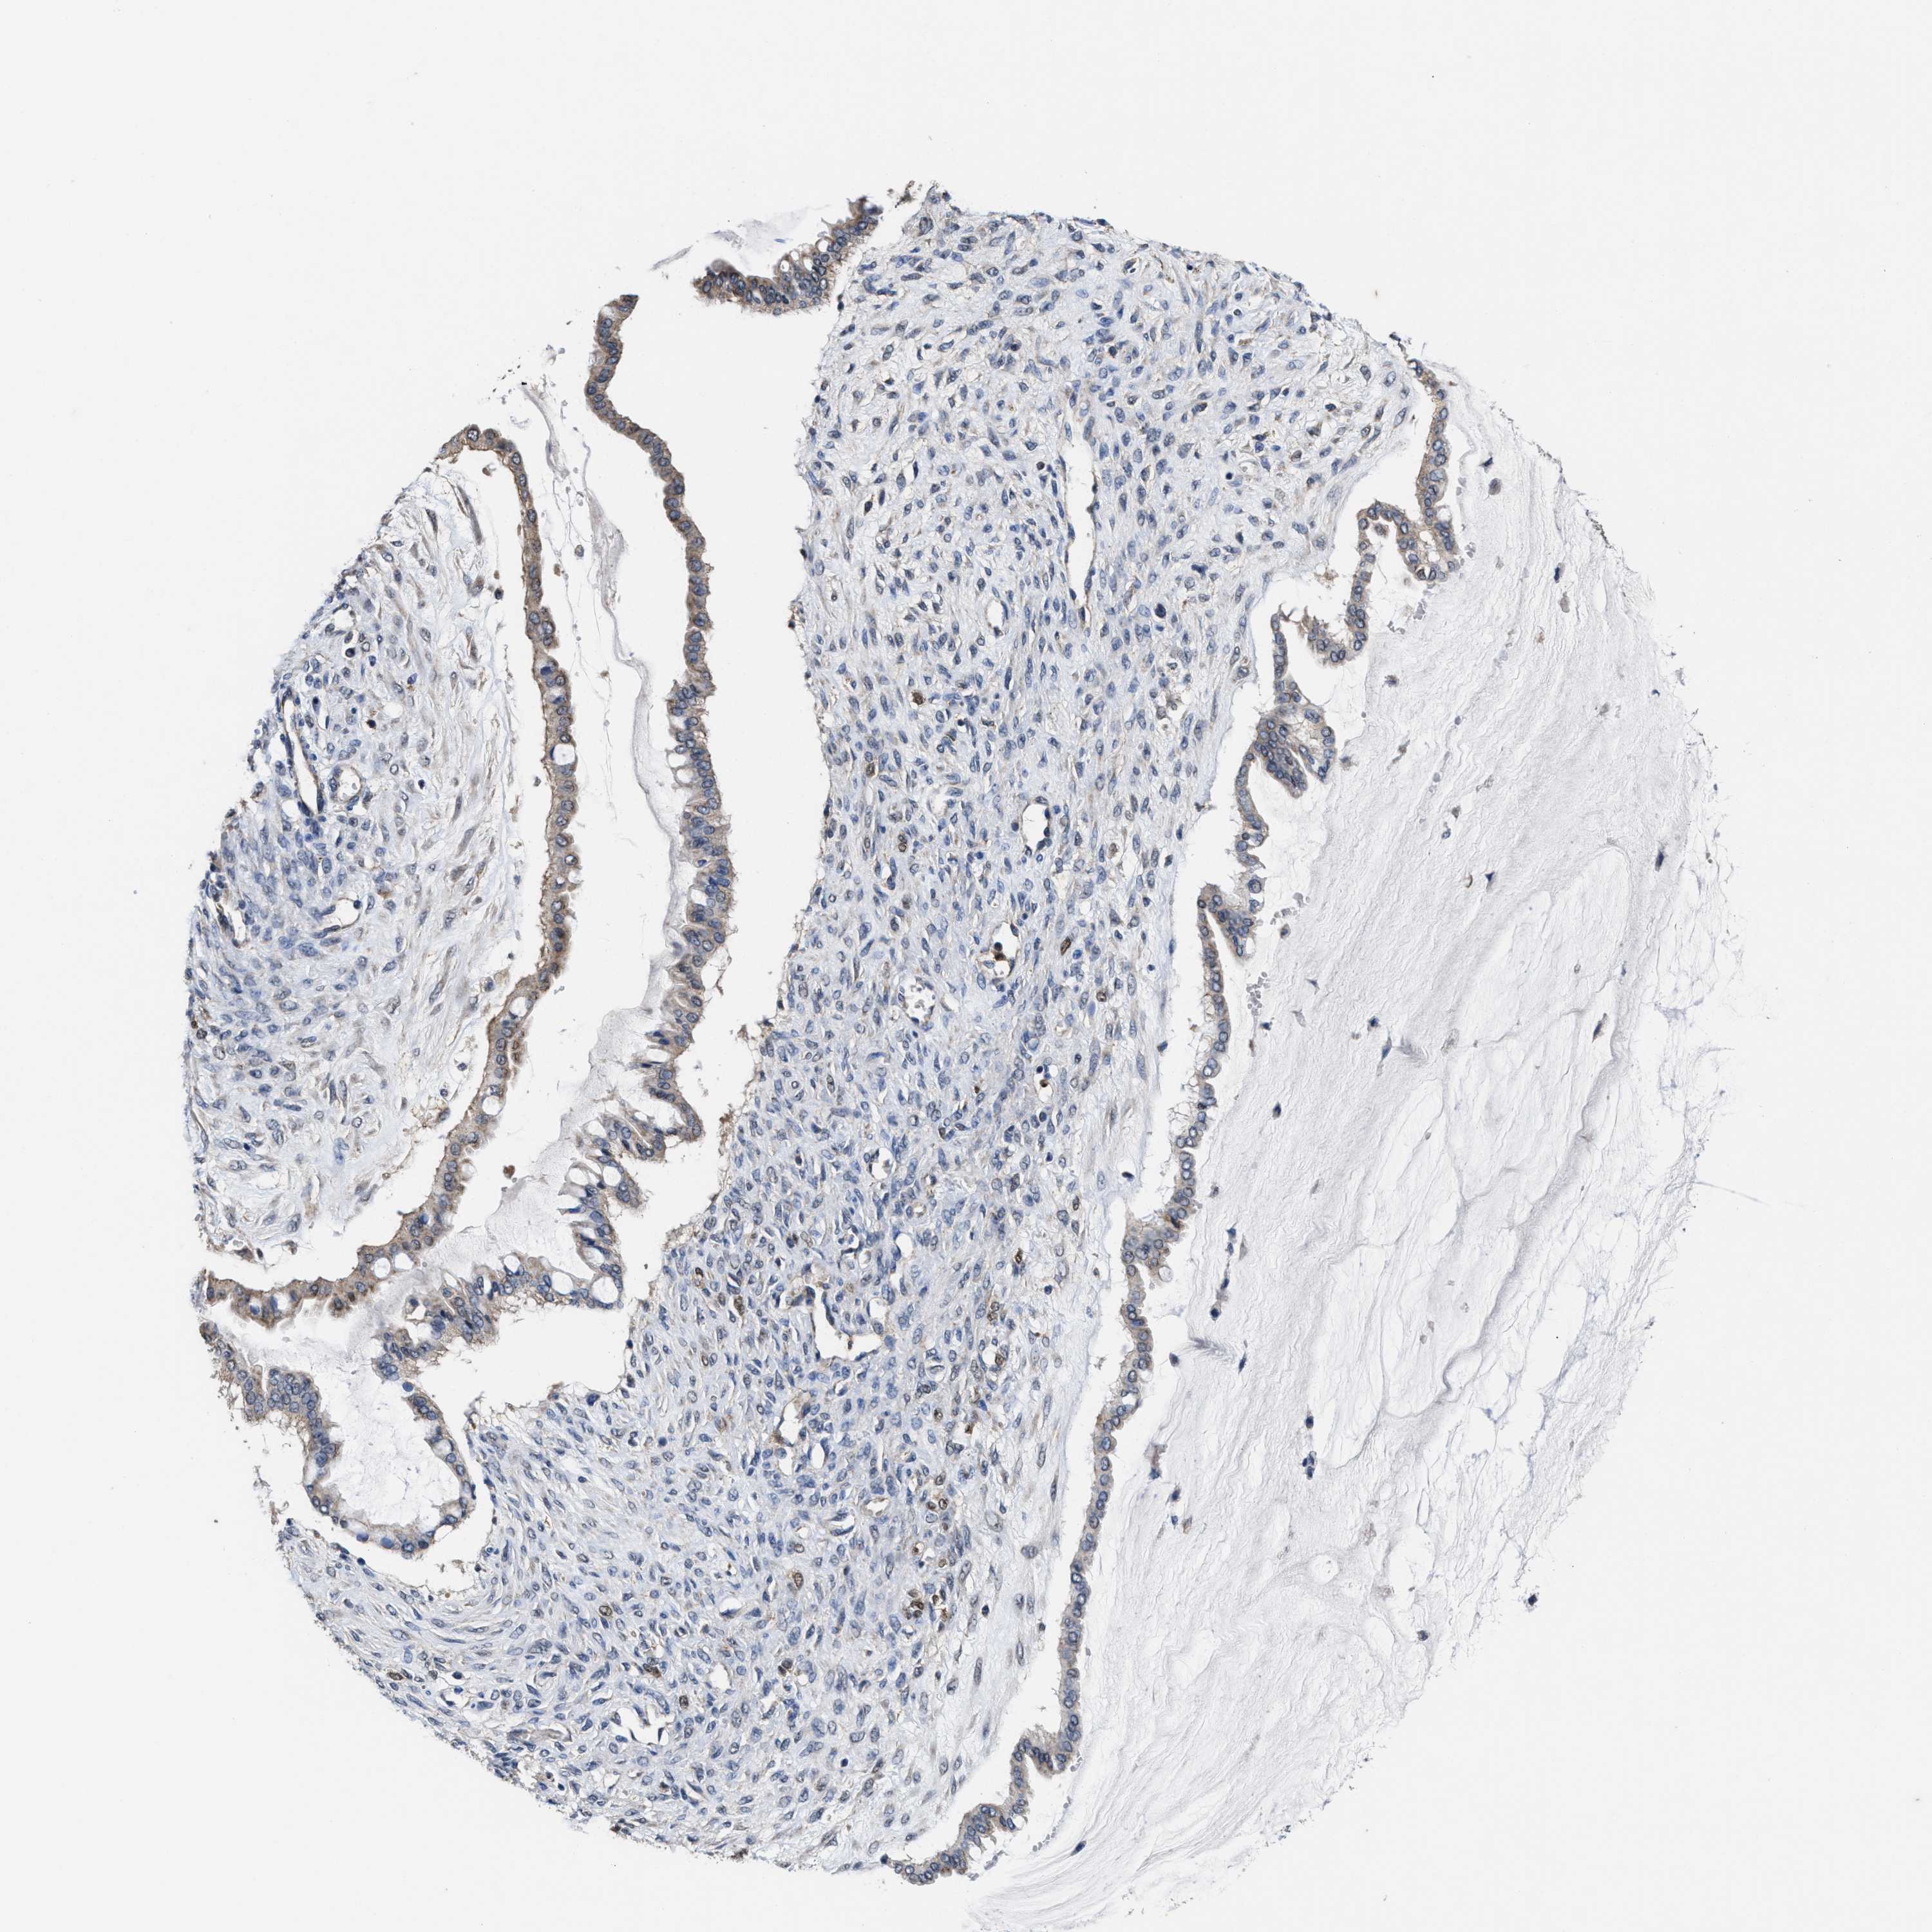

OVARIAN CANCER - Protein expressioni

A mouse-over function shows sample information and annotation data. Click on an image to view it in a full screen mode. Samples can be filtered based on level of antibody staining by selecting one or several of the following categories: high, medium, low and not detected. The assay and annotation is described here.

Note that samples used for immunohistochemistry by the Human Protein Atlas do not correspond to samples in the TCGA dataset.

Antibody stainingi

Antibody staining in the annotated cell types in the current human tissue is reported as not detected, low, medium, or high, based on conventional immunohistochemistry profiling in selected tissues. This score is based on the combination of the staining intensity and fraction of stained cells.

Each image is clickable and will lead to virtual microscopy that enables deeper exploration of all samples and also displays staining intensity scores, fraction scores and subcellular localization as well as patient and tissue information for each sample.

HPA022434

HPA022953

HPA022959

HPA028758

CAB007783

Staining

Cystadenocarcinoma, serous, NOS

Carcinoma, NOS

Carcinoma, endometroid